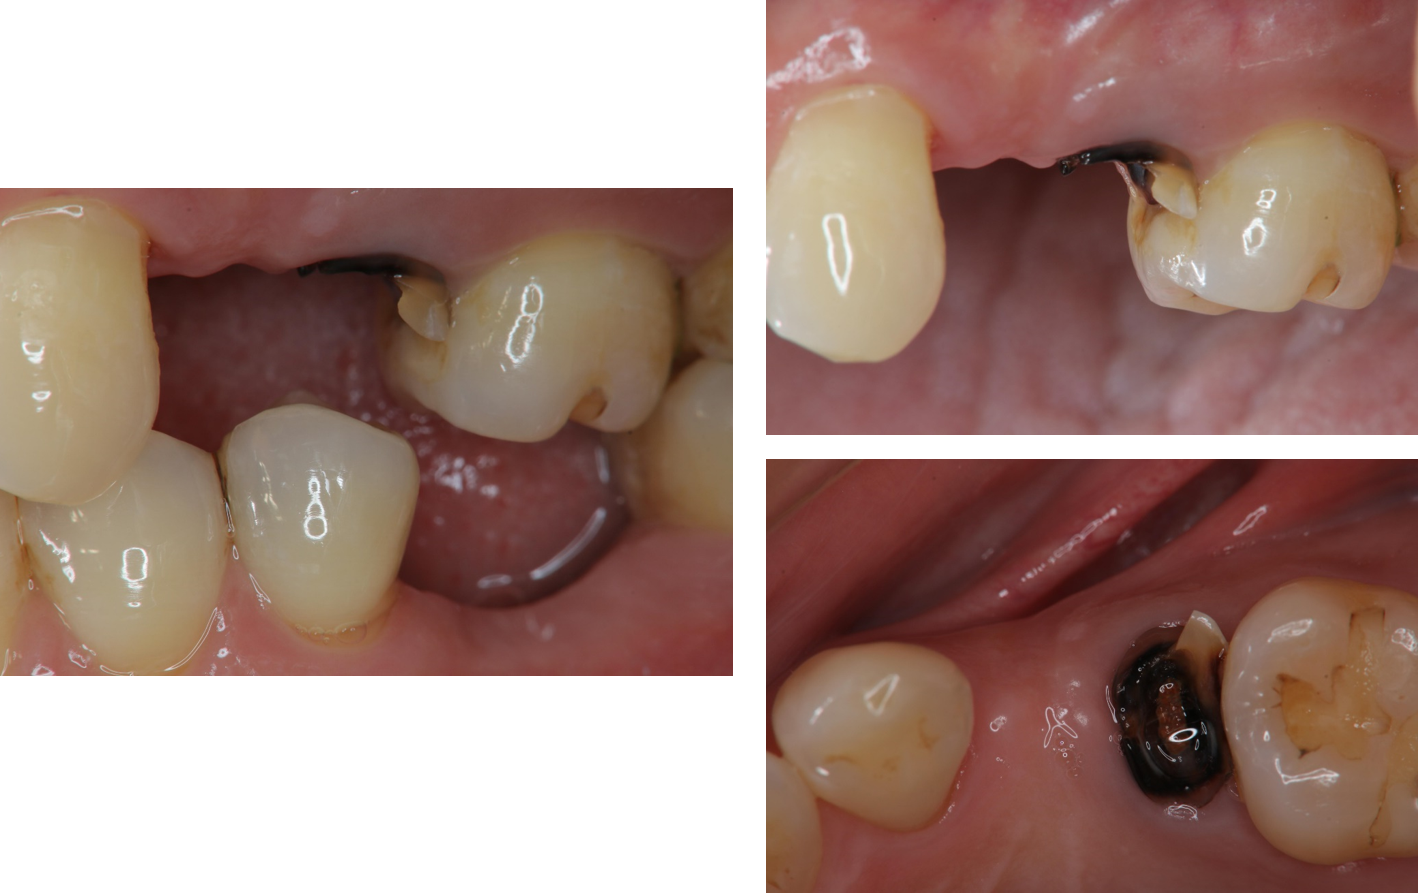

治療前,左下第一大臼齒嚴重蛀牙

治療前,蛀牙至牙根處